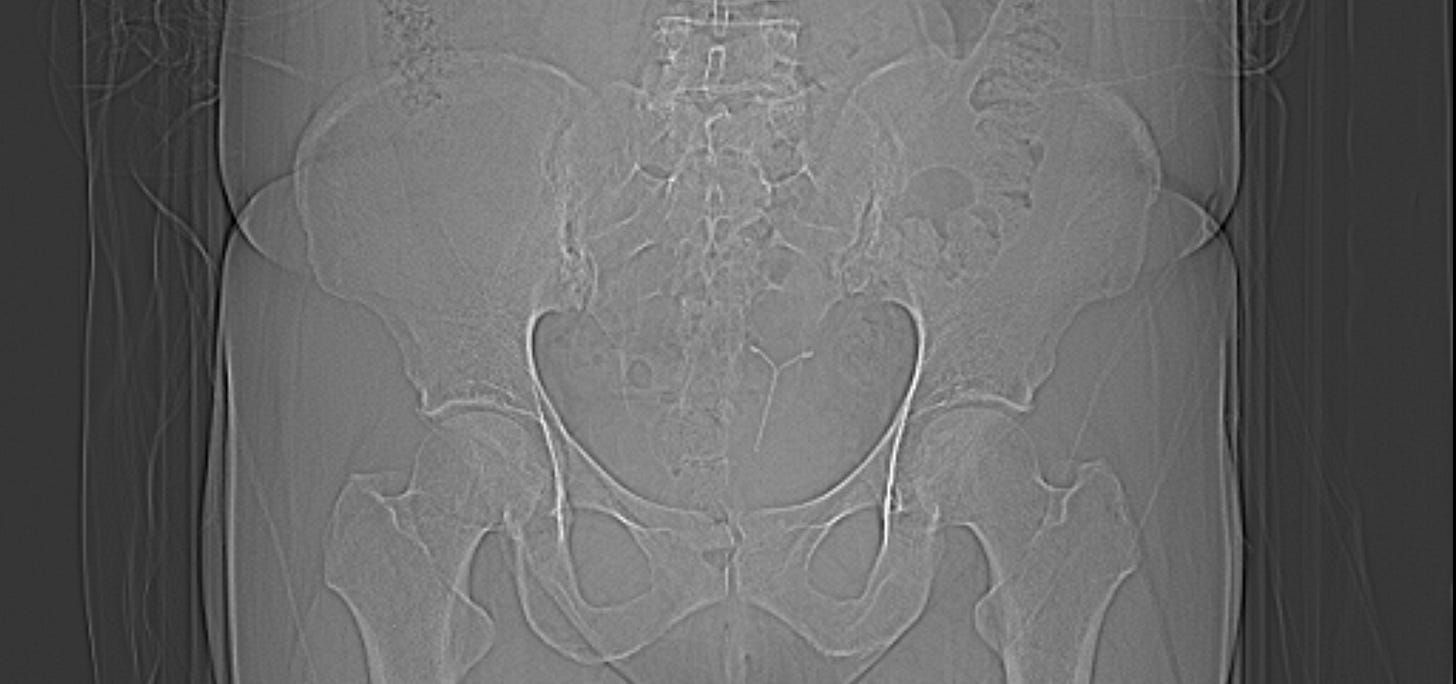

The purpose of the scan is to ascertain whether the coil has perforated the uterus. I already instinctively know that it has. He rolls a sheath onto the probe, squirts gel onto the long wand that looks like a dildo and jams it up inside me. I grunt in pain and swallow the sick that has risen into my throat. He is rough, impatient and fails to describe what he is doing to me. Silent tears roll down my face as he is inside me. I feel such a dark and primal shame and something in me wants it all to end, for me to end. It has been too much to bear. I know that I am being unceremoniously marched back to the other place and I don’t think I can face it again. As he pokes and jabs I look over at the chaperone. She is sat on the other side of the room in a curled up position, hunched shoulders, hands on her knees, eyes resolutely down. She may as well be wearing a T-shirt that says ‘See No Evil, Hear No Evil, Speak No Evil.” The probe is hastily pulled out and he tells me that there is no problem and that the consultation is over. I ask if it is the coil that could be causing the all the issues and the strangest thing happens. He tells me – categorically- that I have no coil fitted. I tell him that this is why this consultation is taking place- to find the coil. He says that he has no knowledge of this and that it was just a routine ultrasound. I explain that I absolutely know that I do have a coil and that’s what he was supposed to be looking for. He repeatedly tells me that there is no coil and that I am wrong. I lie there and wonder if I am going mad. But I know that I do have one- I felt the strings that morning- so I persist. Again, he says that there is definitively no coil and that I am wrong. I feel bone tired. The years of explaining, apologising, advocating- it’s enough now. But something in me is still fighting and I refuse to leave. Deep in me I know that it will only necessitate another gruelling visit and more penetration if I don’t get this sorted today. I insist that he does more tests to find the coil and he reluctantly sends me for an X ray and CT scans.

Matron arrives and she speaks to the doctor and then to me. When it is just the two of us she says that he had been unable to admit to me that he had been wrong and that instead of apologising he has doubled down into his position. They look at my CT scan and he finally accepts that there was a coil and I am told that it has perforated the uterus. He doesn’t apologise; instead he behaves like he knew there was a coil all along. If I had accepted his diagnosis that day then I would have left the hospital with a perforated uterus and no treatment plan. As it is, I email the surgeon to tell her about the perforation. This is her response.